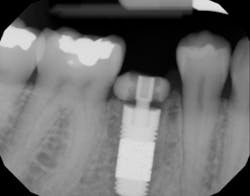

Puros Demineralized Bone Matrix Putty (Zimmer Biomet) was used to fill in the gap between the implant and the socket and to repair the midbuccal fenestration (figure 9A). (3–4) A 4.7-mm x 11.5-mm Zimmer Trabecular Metal implant (Zimmer Biomet) was placed (figure 9B). The implant appeared to have good primary stability, ~45 Ncm.

A custom healing abutment was fabricated using provisional abutment (Temp Abutment, Zimmer Biomet) and bisacryl resin (Integrity, Dentsply Sirona). The healing abutment was placed and tightened by hand (figure 10). Postoperatively, a periapical radiograph was taken demonstrating good prosthetic positioning, and no damage to adjacent anatomic structures (figure 11).